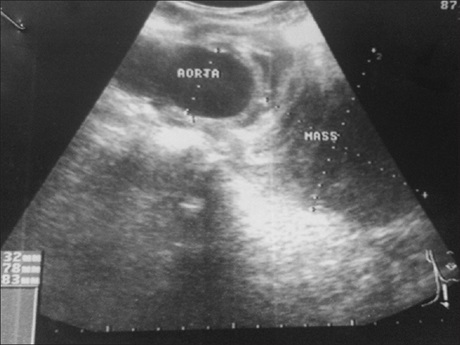

Congenital atresia of the common iliac artery is rare. A case of atresia of the left common iliac artery in a 40-year-old mother of three which was complicated by saccular aneurysm of the terminal abdominal aorta is reported. Radiological investigations revealed massive and complete thrombosis of the aneurysmal sac. Atresia of the proximal left common carotid was confirmed at surgery. Postoperative follow-up radiological investigations show return to normal caliber of the abdominal aorta.